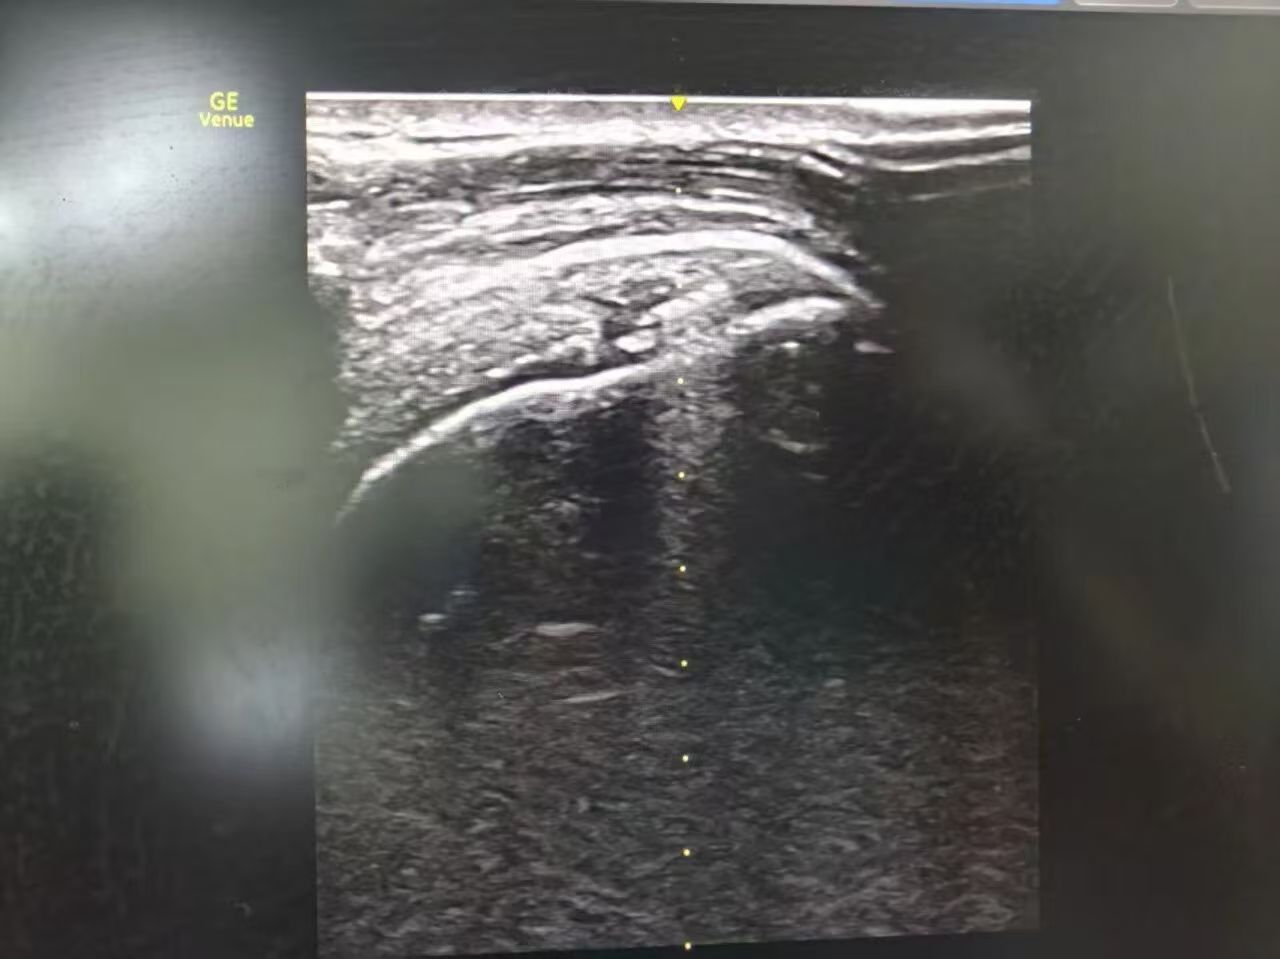

首先,整个治疗全程在超声引导下实施,它实现了“精准解痛+根源修复”双重作用,既通过神经松解和手法松解快速缓解疼痛、改善活动受限,又借助PRP注射从根源修复受损肌腱、减轻炎症,避免症状反复;其次,手术创伤小,仅仅几个针眼,术中基本无出血,术后恢复快,对患者日常生活干扰小;再者,安全性高,PRP源自患者自身血液,无外源物质引发的过敏、排异风险,且臂丛麻醉下患者术中无明显痛苦;术后医生会根据患者具体病情指导正确肩关节功能力量锻炼,实现个性化治疗,精准解决不同患者的核心问题。